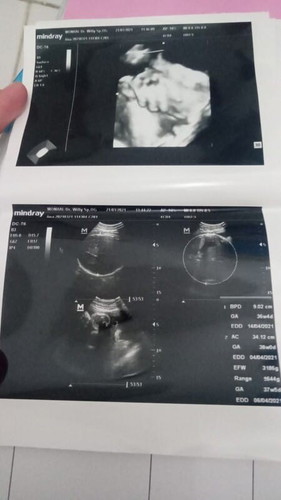

Assalamualaikum bunda mau tanya saya kan waktu hari Minggu USG karena ini udh bulannya hpl nya 31maret tapi dde belum ngajak keluar 😔nah pas saya USG Alhamdulillah hasil nya bagus BB janin sedang cuman 3186g cuman air ketuban banyak tapi udh keruh Bun,eh saya dikasih surat rujukan sama dokter spog nya Bun kalau sampe tgl 23 gak ada mules saya harus diinduksi ke RS metro hospital mau dikasih obat perangsang 😩doain saya Bun mudah mudahan ada keajaiban🙏😇nah disini saya mau tanya soal BPJS juga Bun kan itu bpjs saya rujukan dari bidan terus bidan nya kerja sama sama klinik itu eh sekarang berubah karena saya harus dirujuk ke RS metro hospital ,apa faskes nya harus diganti jadi RS metro hospital apa gimana Bun? tolong yang tau komen ya Bun makasih maaff kepanjangan🙏🤗